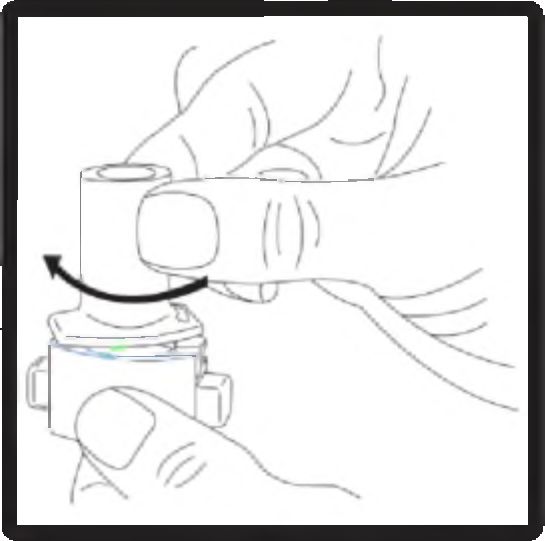

4. Ağızlığı “klik” sesi duyana kadar çevirerek kapalı duruma getiriniz.

5. Tozu kapsülden serbestlemek için:

Not: Kapsül bu aşamada parçalanabilir ve küçük jelatin parçacıkları ağzınıza ya da boğazınıza gelebilir. Fakat jelatin yenilebilir nitelikte olduğu için zararlı değildir.